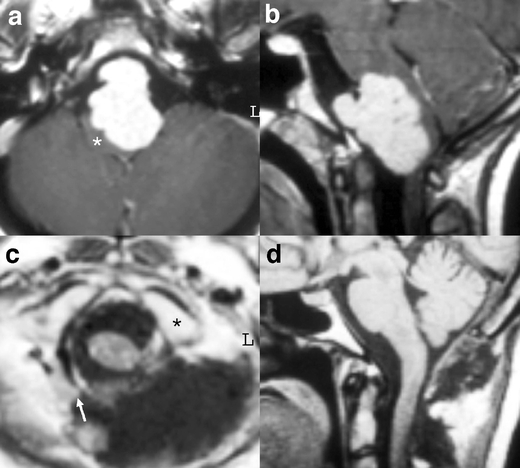

Fig. 3.

a–c Preoperative MRI. A large lateral foramen magnum meningioma displaces the neuraxis. d, e Postoperative CT scan. The meningioma has been completely resected. The spinal cord has regained a normal shape. f Reconstructed 3D CT scan after contrast administration. The resection of the posterior arch of the atlas is visible on the right side. The lateral mass of the atlas (star) was left intact. The vertebral artery (arrow) has been elevated from the C1 posterior arch (compare with the left side) during the dissection